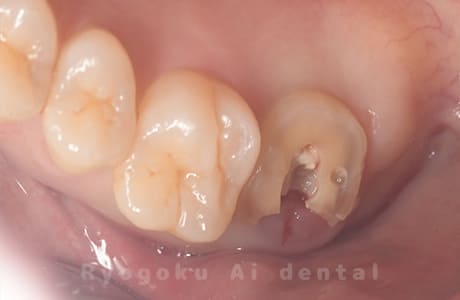

Case03

- 原因

- 急性化膿性根尖性歯周炎

- 治療期間

- 2ヶ月

- 治療内容

- マイクロエンド

- 治療費用

- 121,000円

黙っていても痛みが出るとのことで来院した患者様です。本治療は症状もあるため、抜髄治療をマイクロエンドで行いました。